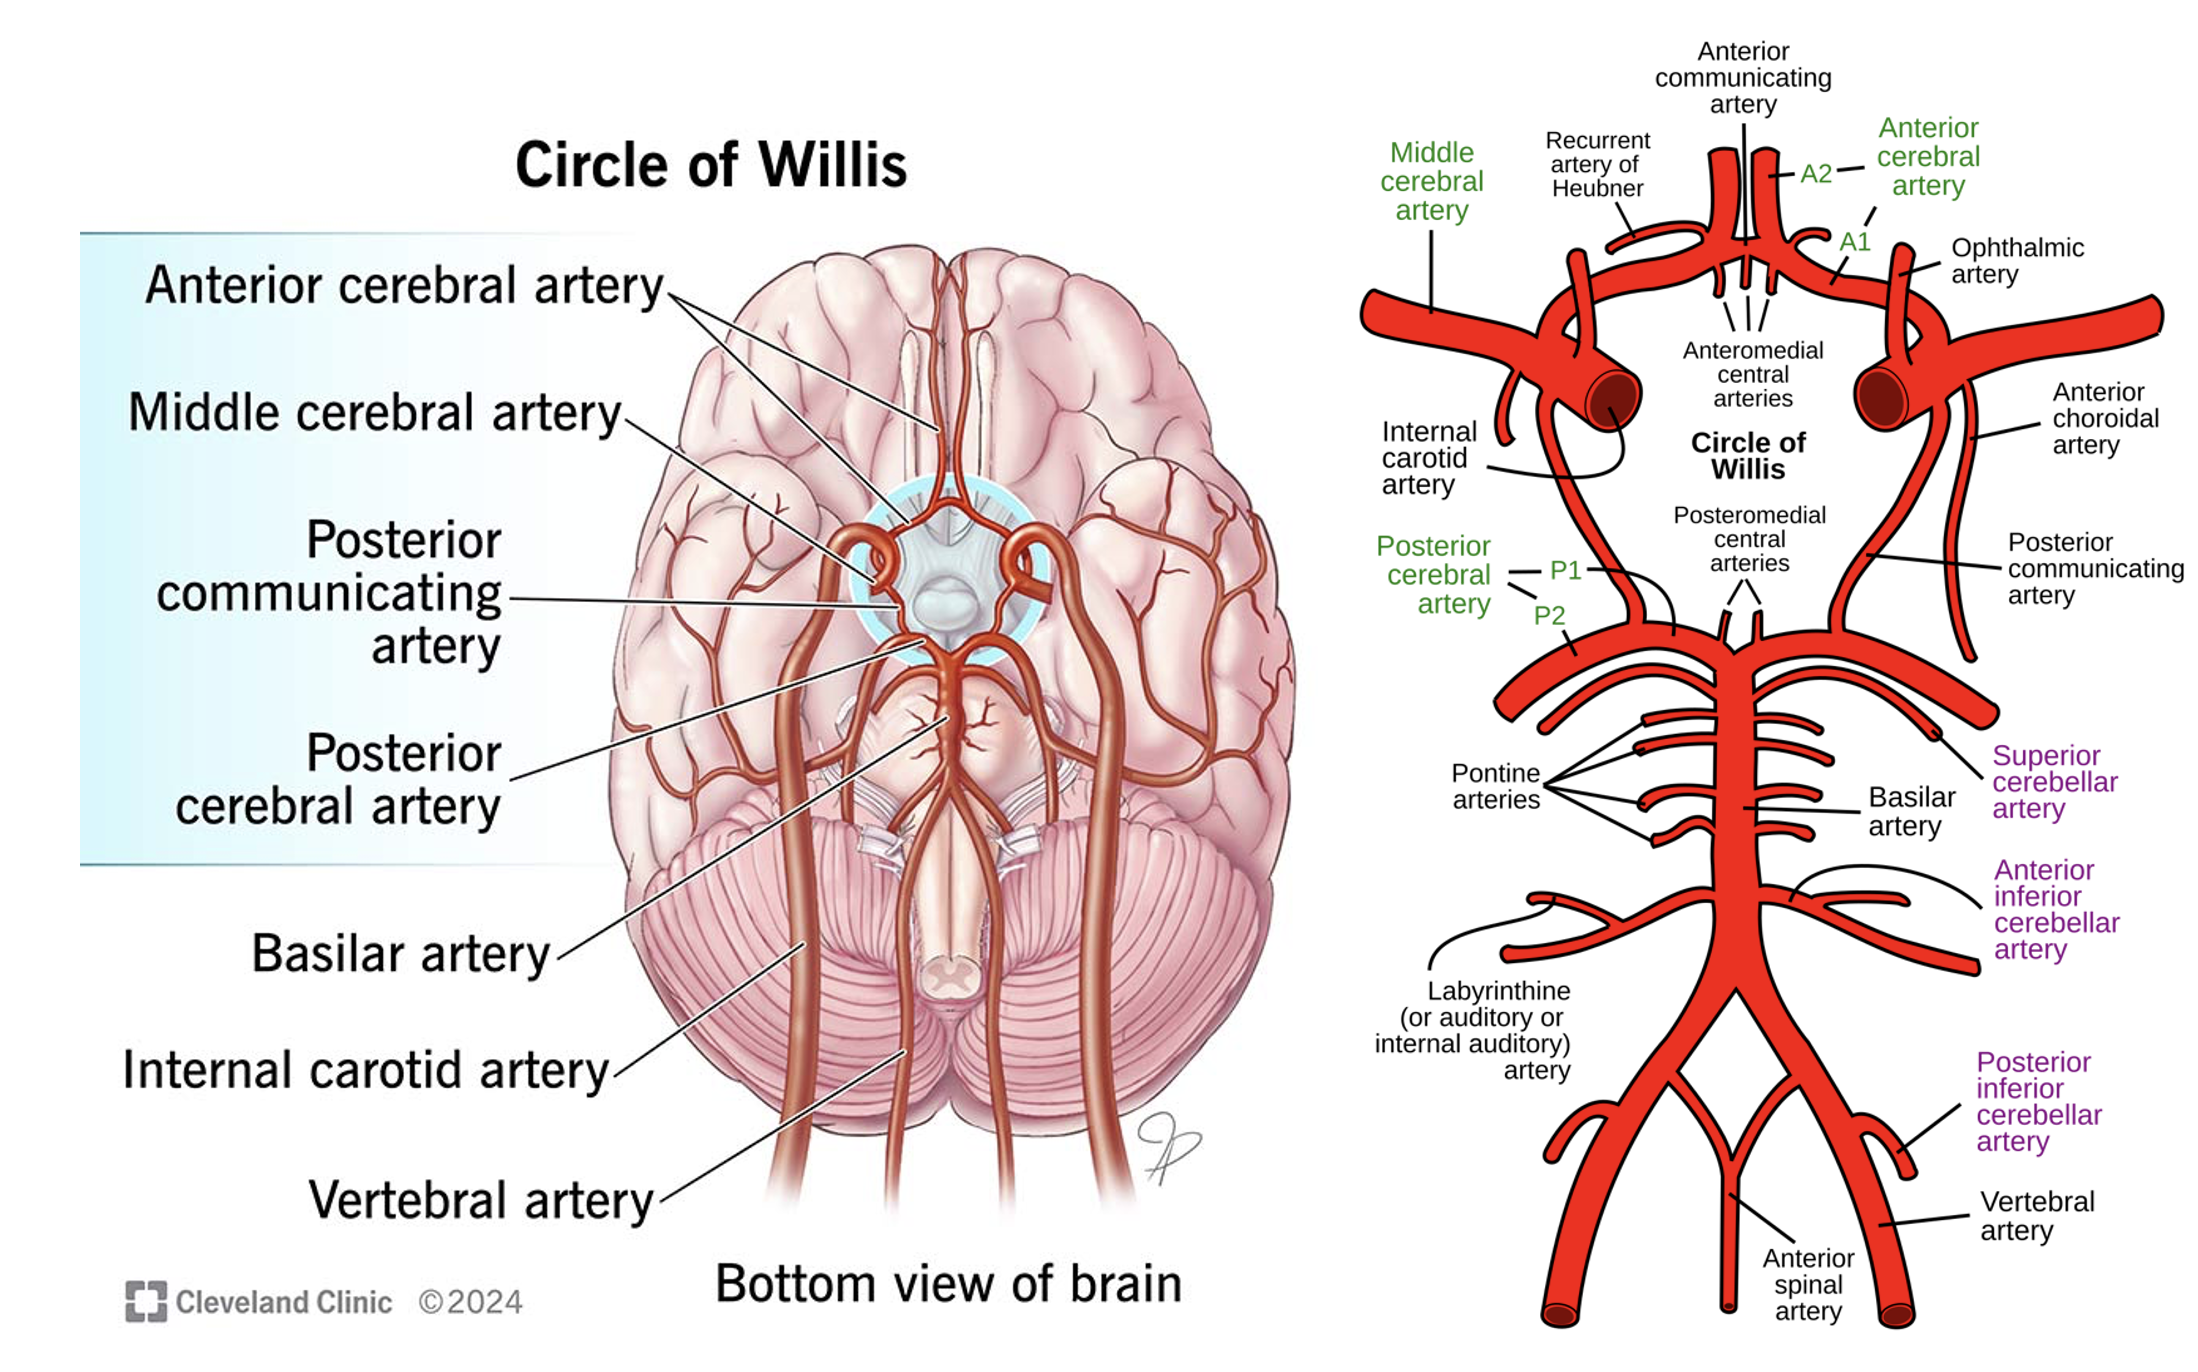

Circle of Willis

3x cerebral arteries – which regions of the cortex do they supply?

3x cerebellar arteries.

3x communicating arteries.

3x ‘other’ arteries (basilar, vertebral, ICA)